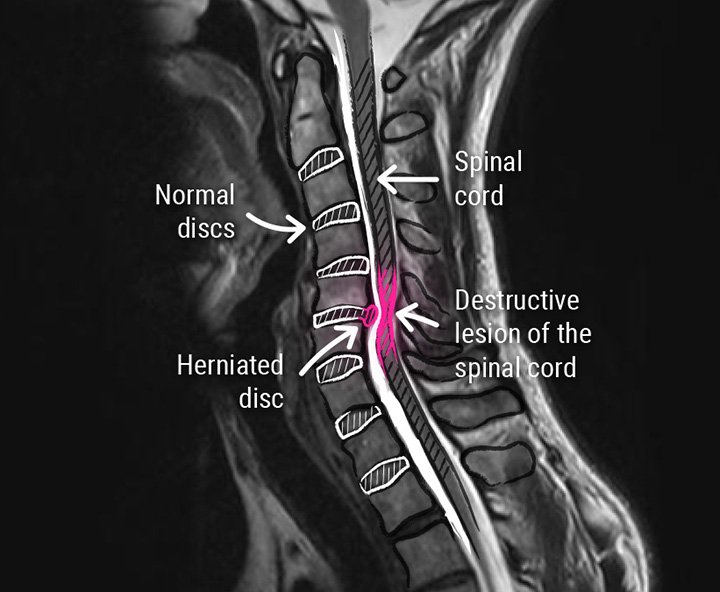

A disc bulge means the inner part of the disc is pushing outward but still contained within the outer ring (annulus fibrosus). The shape changes, and pressure can increase, but nothing has ruptured.  This is also often known as a disc tear because some of the fibres have lost their integrity.

A true herniation means the inner material (nucleus pulposus) has broken through a tear in the annulus, creating a higher chance of nerve irritation, and is very serious.

A slipped disc may refer to a bulge or a herniation, but a bulging disc is still contained, and a herniation is not.